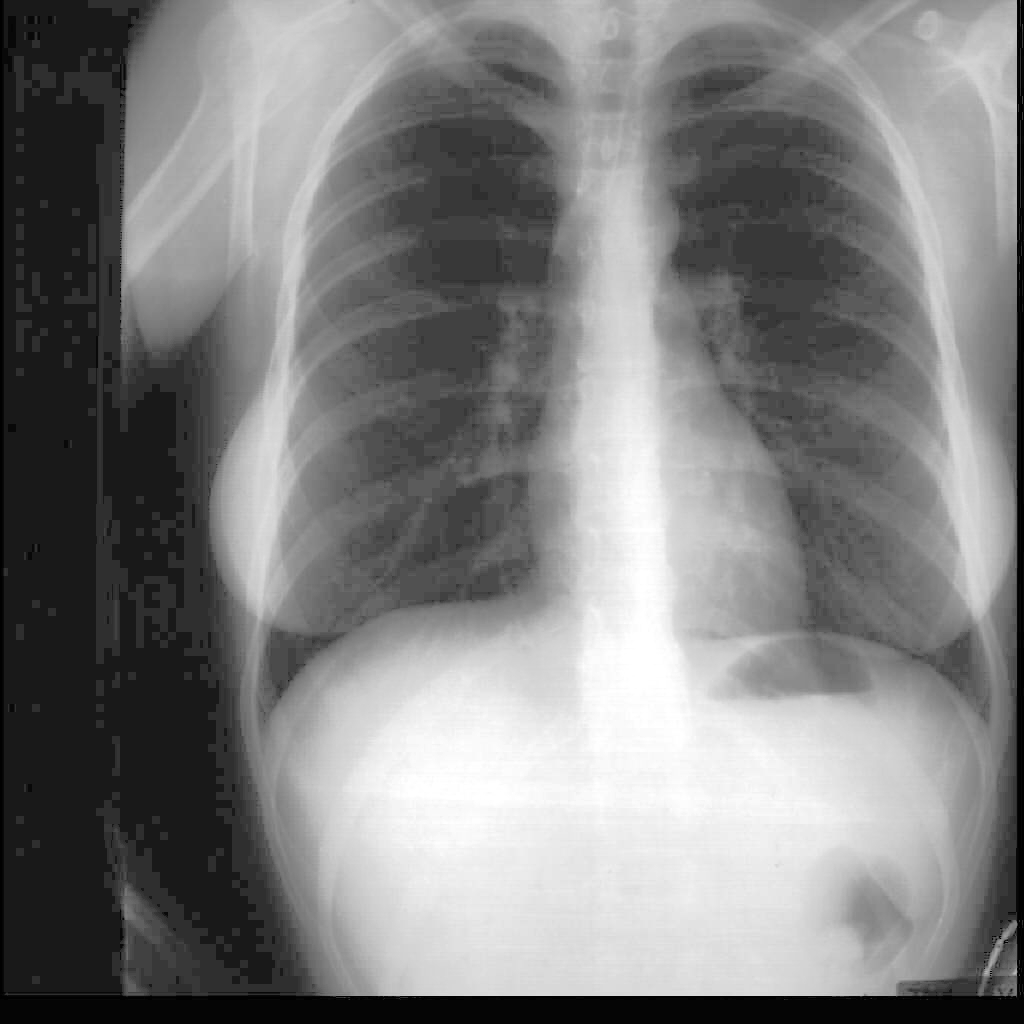

Ejemplo de visualización de zonas oscuras por linearización (ecualización) de la función histograma

En radiografías digitalizadas es muy frecuente la existencia de zonas excesivamente blancas (sobreexpuestas o excesivamente negras (subexpuestas) en las que se hace difícil poder observar los detalles. En este tipo de imagen suele se poco eficaz la simple expansión del histograma, ya que ambos extremos, negro y blanco, suelen estar presentes en la misma. La linearización o ecualización de los niveles de gris puede ser una forma eficaz para resaltar o mejorar la visualización de la zonas oscuras, sin que se pierdan los detalles, por saturación, en el resto de la imagen.

Efecto de la linearización o ecualización de la función histograma sobre la imagen anterior. El proceso mejora la visualización de las zonas oscuras sin que se pierdan detalles en las zonas más claras de la imagen.